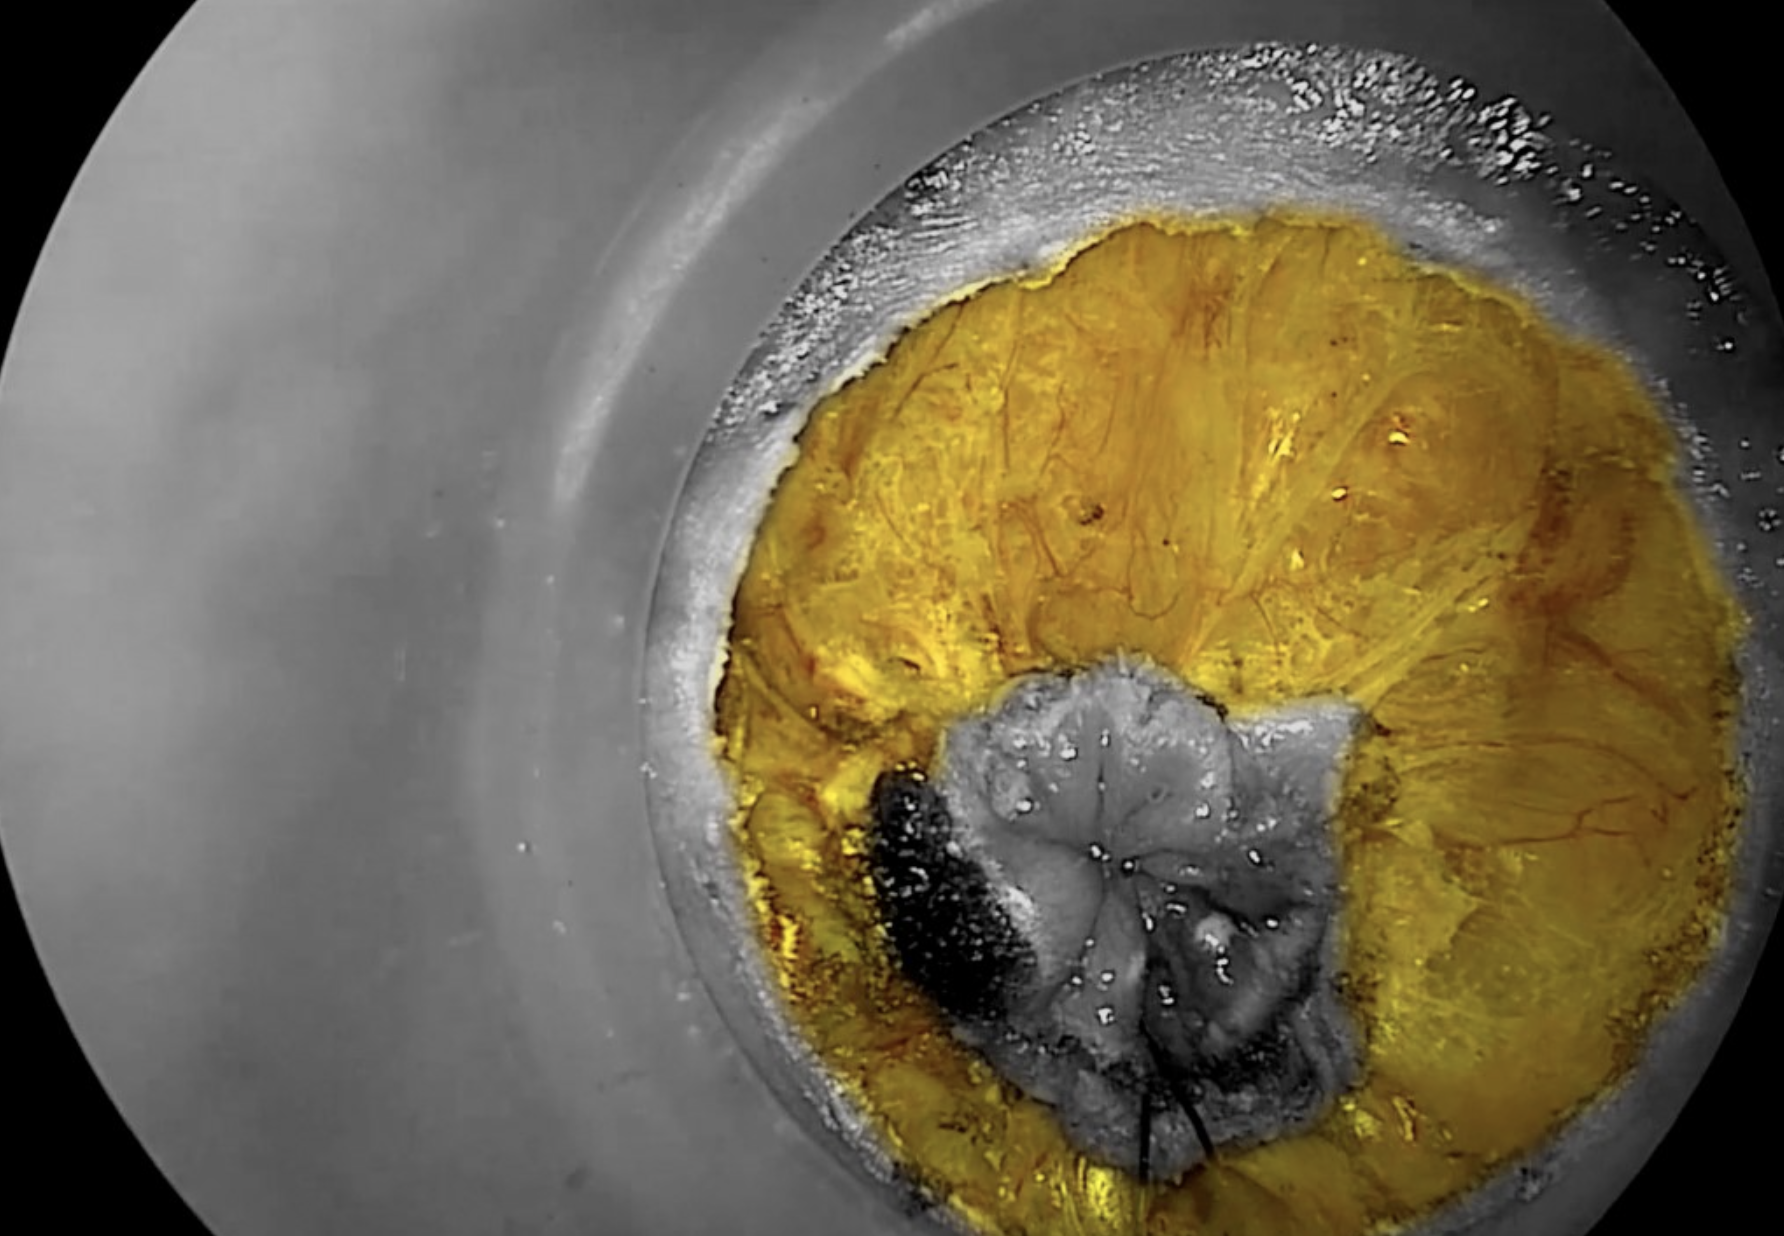

Copyright Dr. Joep Knol

Diathermy marking of rectal mucosa to guide initial dissection. The contrast picture shows the distal rectal excision margin.

Diathermy hook dissection of the mesorectum, with yellow contrast showing entry into the correct mesorectal plane.

Circumferential entry into the correct mesorectal plane, highlighted in yellow.